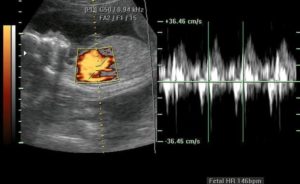

Частота ритма изменяется:

- на сроке 6-8 недель частота составляет от 110 до 130 ударов в минуту;

- на 9-й…10-й неделях ЧСС (частота сердечных сокращений) – 170-190 ударов в минуту;

- начиная с 11-й недели – от 140 до 160 ударов в минуту.

Кроме обнаружения сердцебиения, при помощи УЗИ определяется частота сердечных сокращений (ЧСС), то есть, сколько раз за минуту бьется сердце.

Изменение этого показателя связано с особенностями вегетативно-нервной системы плода, отвечающей за функционирование его внутренних органов. Так, в зависимости от того, сколько недель составляет беременность, сердцебиение варьируется в следующих пределах:

- на 6-8 неделе — 110-130;

- на 9-10 неделе — 170-190;

- 11-40 недель — 140-160.